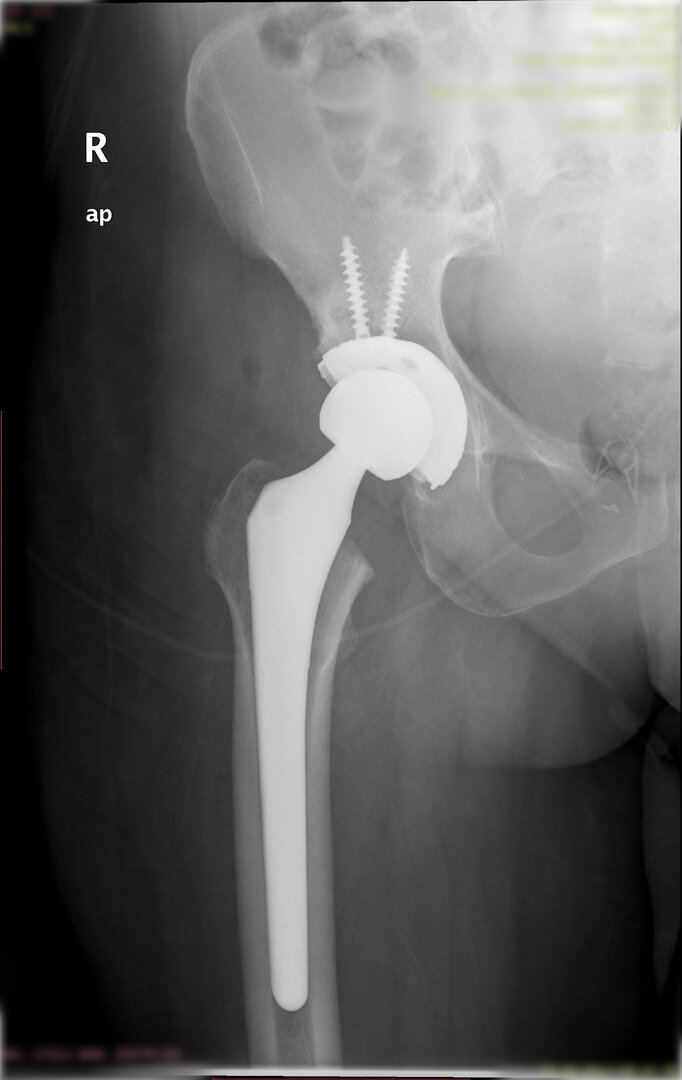

Peki kalça protezi ameliyatın da neler yapıyoruz? Diz protezi ameliyatındaki benzer aşamaları uyguluyoruz. Kalça eklemi dize göre yapısal olarak ve çalışma sistemi olarak farklıdır. Kalça eklemi bir yuva ve onun içinde hareket eden femur başı dediğimiz bir toptan oluşur. Kalça eklemi kireçlenmesinde bu baş ve yuva yüzeyindeki kıkırdakların aşınması sonucu başın yuvarlaklığı kaybolur, sonuçta ağrı ve hareket kısıtlılığı ortaya çıkar. Bu yüzeyleri değiştirirken öncelikle bu başı kesip atıyoruz. Daha sonra yuvayı yine kılavuzlarla oyup uygun büyüklükteki protezi sıkıştırdıktan sonra en az 2 vida ile kemiğe adapte ediyoruz. Daha sonra alt uyluk kemiğini yine kılavuzlar yardımı ile oyduktan sonra kemiğe adapte ediyoruz ve sistemi birleştiriyoruz.

Büyütmek için üzerine tıklayınız.